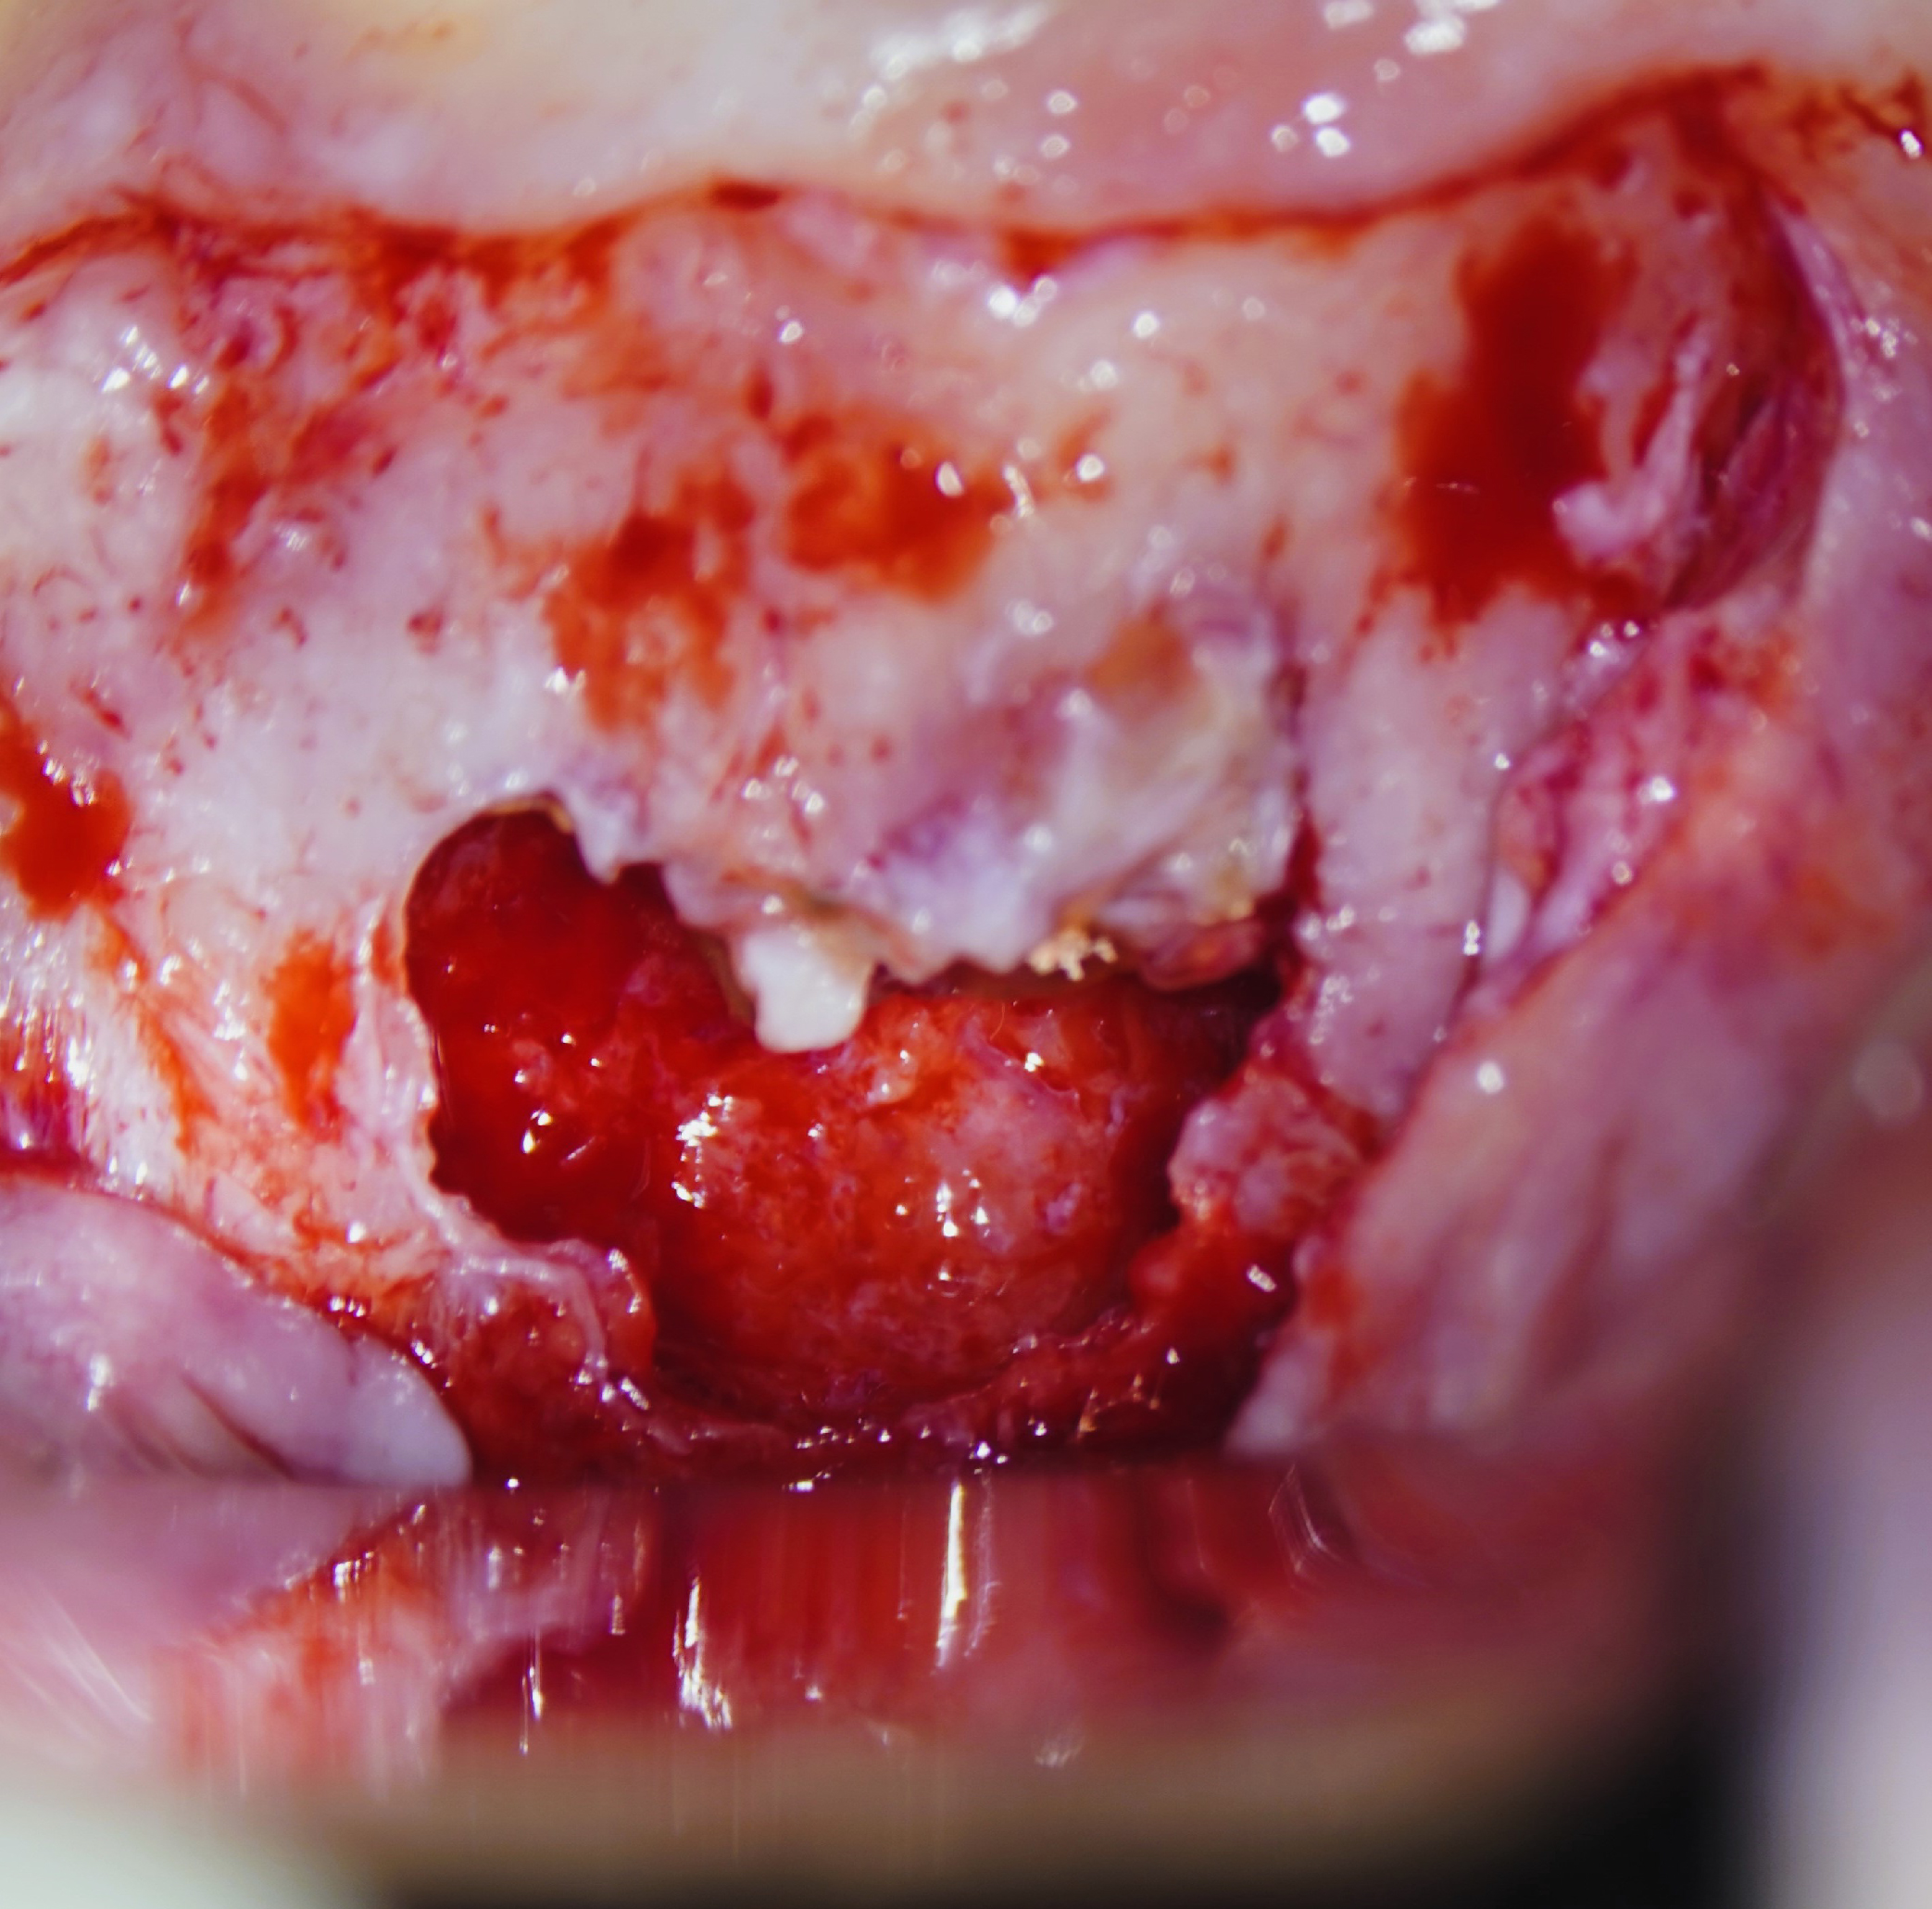

Imágenes del tratamiento

* Haz click sobre las imágenes para verlas a mayor tamaño y a color